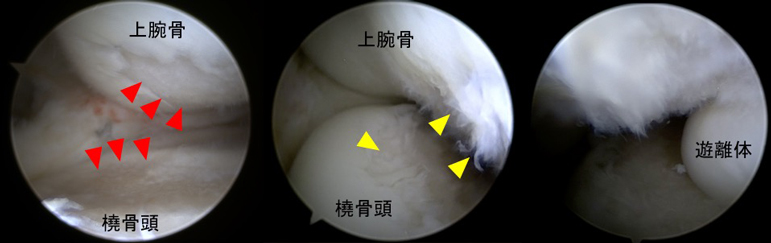

変形性肘関節症の関節鏡所見

(左:前方鏡視、中:後方鏡視、右:肘関節内遊離体)

赤三角部:軟骨が欠損して骨が露出しています

黄三角部:軟骨が線維化し毛羽立っています